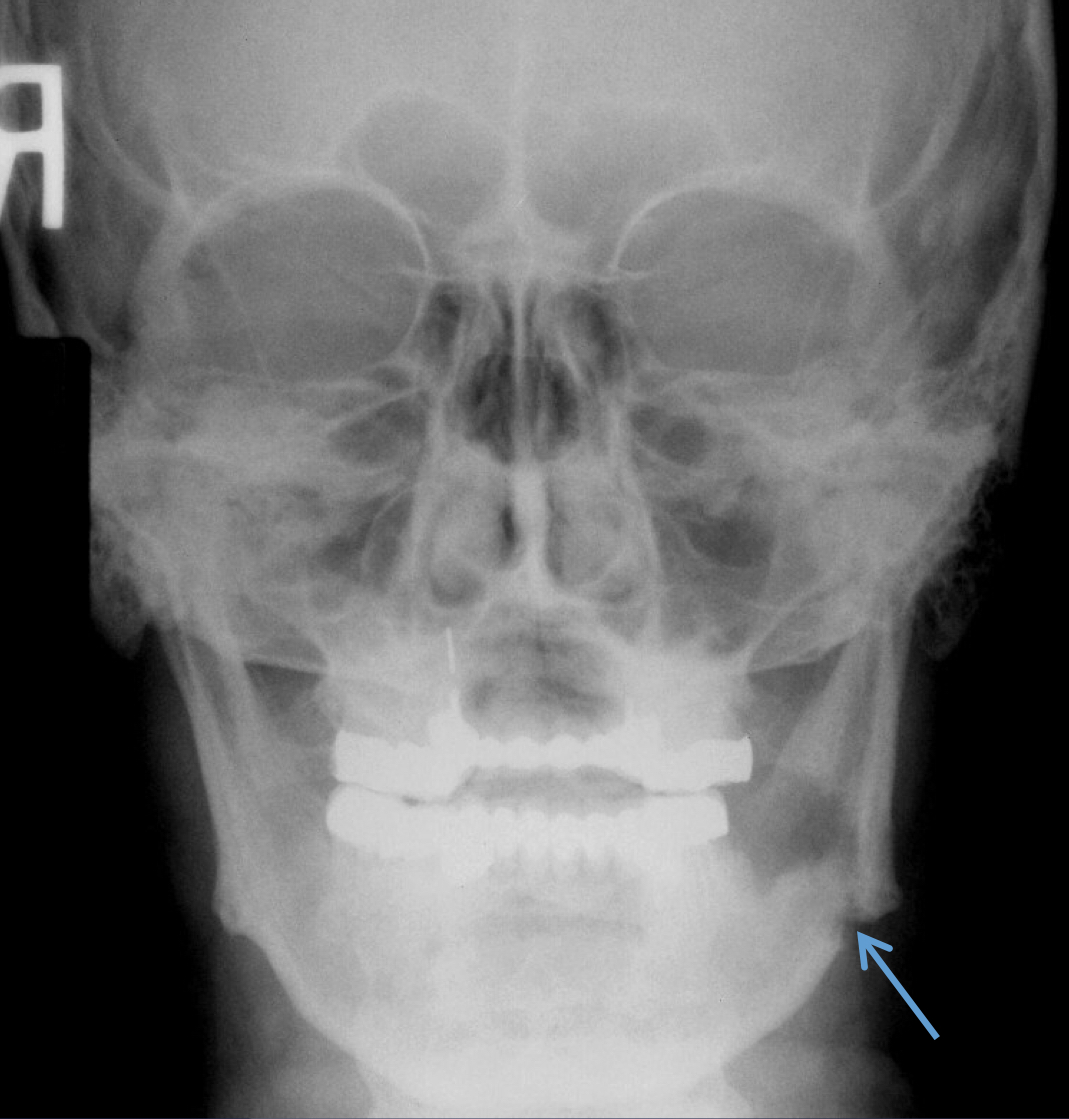

which osteomyelitis?

mandible, PM area

acute osteomyelitis

no radiographic features bc no manifestation in early stages; may vary in stage